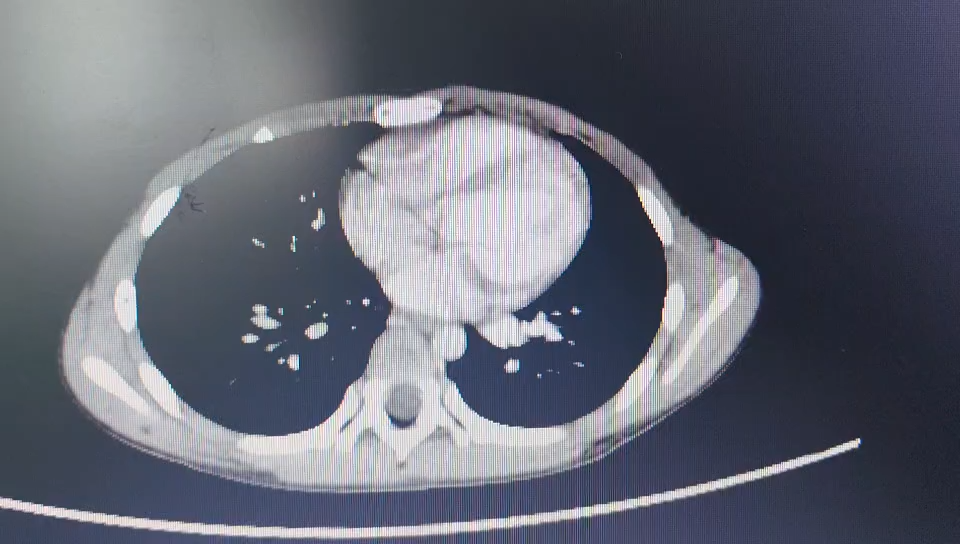

完善上腹部增强CT结果如下: